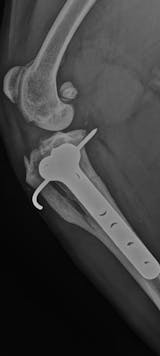

The first photo was taken five months post-surgery, and the second is just one month into using the laser. You can see a big difference already, the crack on the right side has fully healed, and there’s noticeable progress on the left side of the plate as well.

She’s definitely feeling better too, keen to do so much more! But for now, it’s still leash walks and pen rest while she continues to heal.

It’s been a long road, and she sadly had to spend the whole summer on strict rest. But fingers crossed, by next summer she’ll be ready to live life to the fullest again. 💛